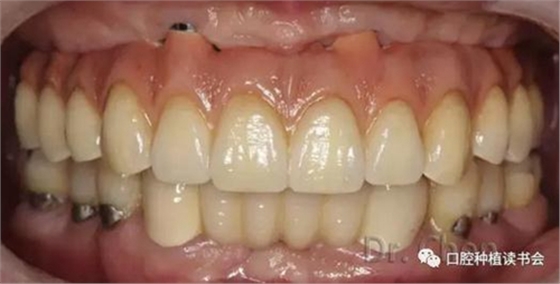

患者佩戴義齒后的口內(nèi)像和口外像(圖11、12),義齒外形、顏色、發(fā)音滿意,

▲口內(nèi)連接全氧化鋯一體橋后

▲上頜佩戴固定橋后的微笑像